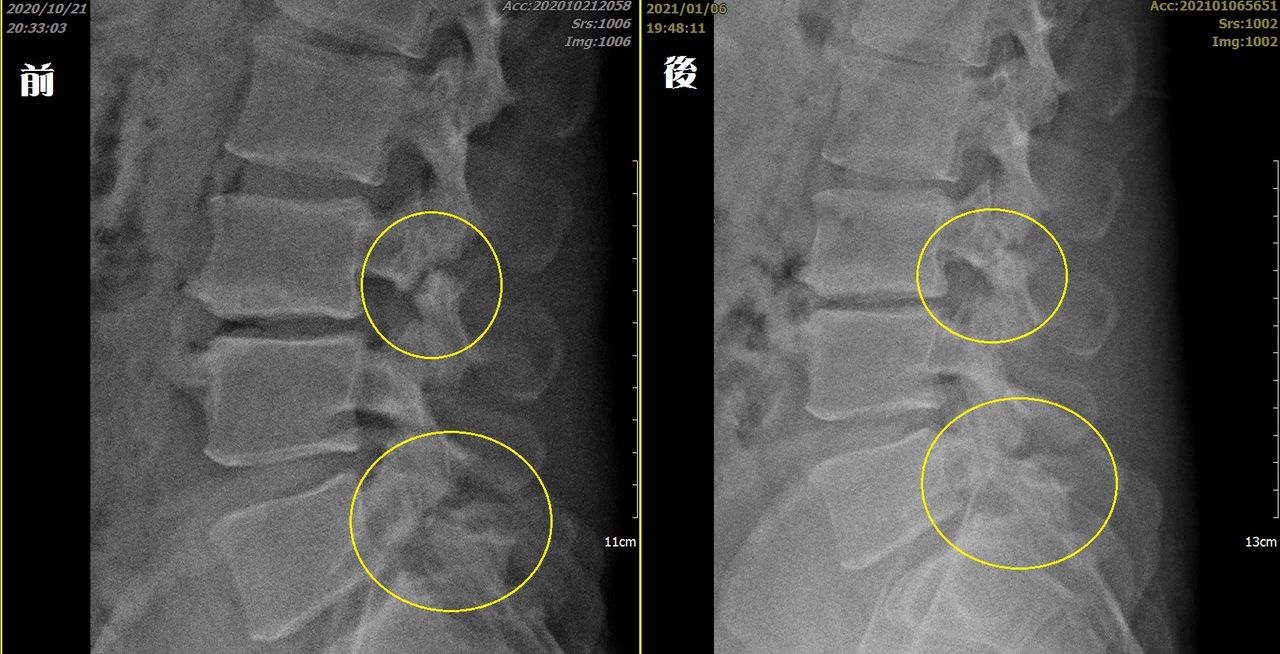

司機跌倒致椎弓兩處骨折進階水介質震波讓骨癒合 生活新聞 生活 聯合新聞網

椎弓解離 椎弓解離怎麼治療 需要開刀脊椎手術嗎 熱河診所

司機跌倒造成腰椎椎弓兩處骨折 非侵入性水介質震波讓骨癒合 華人健康網